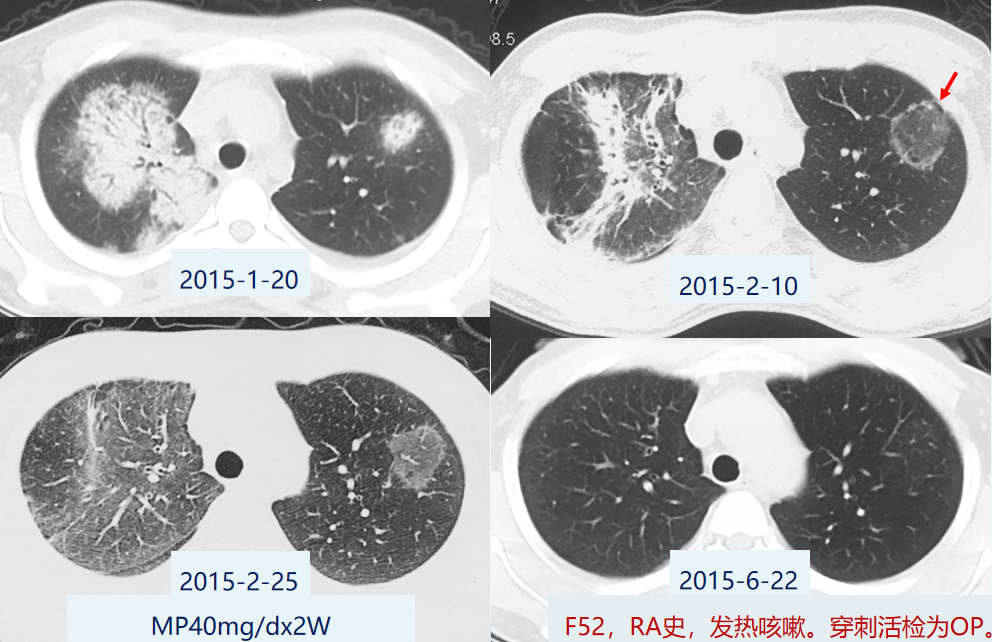

病例2:

35岁男性肺结核患者,发热、咳嗽、纳差2月,体重下降8kg,双肺少量爆裂音。肺CT:左胸膜增厚,左胸廓塌陷,右下肺可见反晕征。仔细看反晕征的外壁和中间都有很多微结节。[1]

病例3:

女性,59岁,粟粒性肺结核的基础上,双肺弥漫微结节伴反晕征。[2]

病例4:

女性,38岁,肺结核。左肺上叶反晕征,外壁有结节。[2]

病例5:

女性,39岁,COP。反晕征相对均匀光滑,无结节。[2]

病例6:

男性,36岁,肺结核。反晕征由微小结节构成。[2]

病例7:

女性,36岁,COP。反晕征光滑无结节。[2]

以上主要对比了肺结核与机化性肺炎的反晕征。机化性肺炎的反晕征相对质地均匀光滑,无结节。肺结核的反晕征则比较粗糙不均,仔细看其实是由无数个小点(微结节)「拼凑」成的,这与结核作为肉芽肿的病理特征也是相符合的。